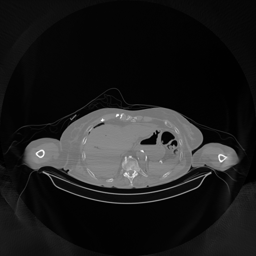

The results for simulated noisy data are shown in Fig. 2. The first and third rows display two representative slices from the test set, and the second and fourth rows present the corresponding error maps. The traditional WCE method suppresses cupping artifacts and recovers some missing anatomical structures but still shows noticeable deviations from the ground truth. Predictions from the four diffusion-based models demonstrate a markedly improved ability to restore anatomical structures. Among them, cDDPM fails to fully reconstruct the patient bed and retains residual noise in its outputs. This noise is attributable to an incomplete reverse denoising process rather than residual Poisson noise, as evidenced in our noise-free experiments (Fig. 5 in the Appendix). PatchDiffusion, diffusionGAN, and I2SB achieve similar visual quality, with I2SB producing the cleanest and most consistent reconstructions.

Quantitative results in Tab. V further confirm I2SB’s superiority over conventional deep learning methods such as FBPConvNet and Pix2pixGAN across RMSE, PSNR, and SSIM. Compared to other diffusion models—including cDDPM, PatchDiffusion, and cLDM—I2SB delivers higher image quality, while diffusionGAN achieves comparable quantitative performance. However, I2SB demonstrates a significant advantage in inference efficiency, as summarized in Tab. IV.

The experimental results on clinical head data are shown in Fig. 4. The reference images were reconstructed using the fast iterative shrinkage-thresholding algorithm (FISTA) with total variation regularization from non-truncated projection data. In the WCE reconstructions (Fig. 4(b)), severe truncation prevents accurate recovery of anatomical structures outside the FOV. Despite being trained solely on simulated data with a domain gap, all deep learning models can restore a substantial portion of the missing anatomy. Among them, the diffusion-based methods recover soft-tissue boundaries more faithfully than the conventional deep learning approach FBPConvNet, highlighting their stronger image generation capability. However, cDDPM reconstructions exhibit more noticeable noise than those from other methods, consistent with the simulated data results. The patchDiffusion model introduces artifacts within the FOV, likely due to its patch-wise processing strategy. While I2SB shares the same limitations as other diffusion models in perfectly restoring soft-tissue detail, it produces fewer residual noise patterns and fewer artifacts within the FOV boundaries. Overall, Fig. 4 demonstrates the strong efficacy of I2SB in reconstructing real CBCT data.